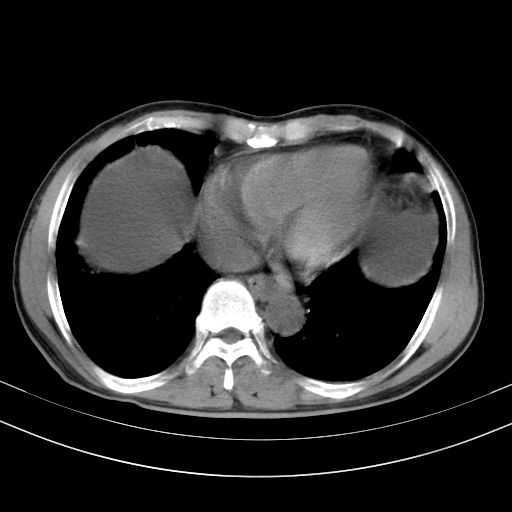

以下是引用随光逐影在2010-2-28 10:23:00的发言:[br]1)考虑肝癌;建议行ct增强扫描检查。2)肝硬化,脾大,腹水。3)慢性胆囊炎。

以下是引用dyqct在2010-2-28 16:44:00的发言:[br][quote]以下是引用随光逐影在2010-2-28 10:23:00的发言:[br]1)考虑肝癌;建议行ct增强扫描检查。2)肝硬化,脾大,腹水。3)慢性胆囊炎。